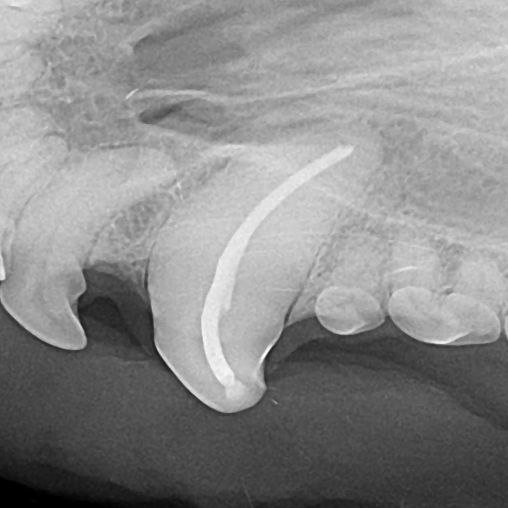

Example of a fractured canine tooth in a dog:

After: